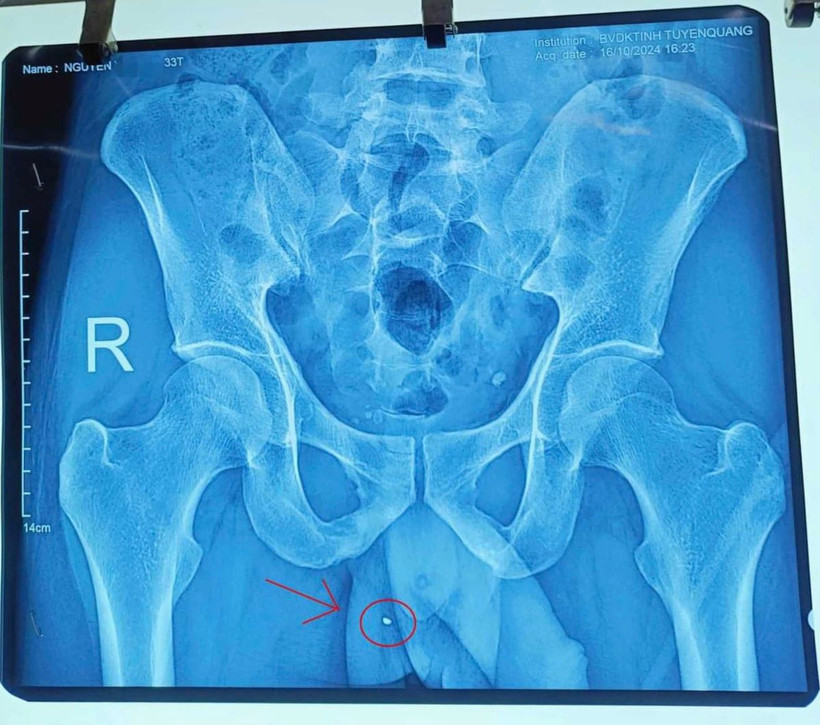

Mảnh kim loại xuyên vào cơ quan sinh dục bệnh nhân. (Ảnh: TTXVN)

Ngay sau khi nhập viện, nạn nhân nhanh chóng được làm các xét nghiệm và chuyển mổ cấp cứu. Qua thăm khám và khai thác thông tin, nạn nhân cho biết, khi làm việc đã sử dụng súng bắn đinh và bị mảnh kim loại văng ra xuyên vào cơ quan sinh dục.

Sau quá trình phẫu thuật, kíp mổ Khoa Ngoại thận - Tiết niệu, Bệnh viện Đa khoa tỉnh Tuyên Quang phát hiện nạn nhân có vết thương ở bộ phận sinh dục và rỉ máu. Kíp mổ phẫu thuật lấy ra dị vật kim khí, kích thước khoảng 4mm, sau đó bảo tồn tinh hoàn và đặt một dẫn lưu cho bệnh nhân.